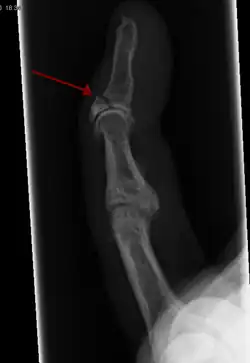

- Broken finger – a fracture of the carpal phalanges

Occasionally, smaller bones, such as phalanges of the toes and fingers, may be treated without the cast, by buddy wrapping them, which serves a similar function to making a cast. A device called a Suzuki frame may be used in cases of deep, complex intra-articular digit fractures.[40] By allowing only limited movement, immobilization helps preserve anatomical alignment while enabling callus formation, toward the target of achieving union.